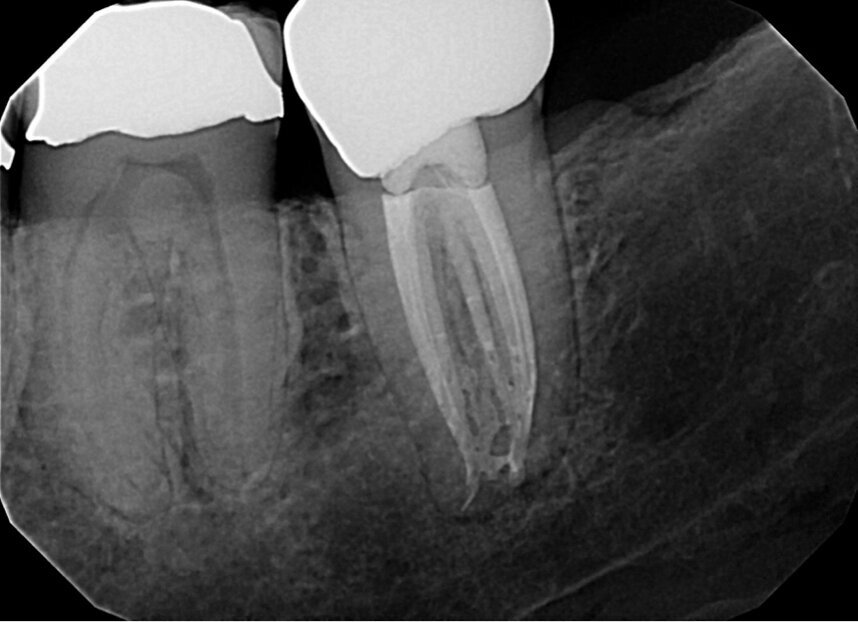

Fig. 13a: Case treated with Chlor-Xtra, SmearOFF with EndoUltra activation. Note the excellent cone fit and apical control of obturation. (Courtesy of Dr. Sam Alborz)

Fig. 13b: Case treated with Chlor-Xtra, SmearOFF with EndoUltra activation. Note the excellent cone fit and apical control of obturation. (Courtesy of Dr. Sam Alborz)